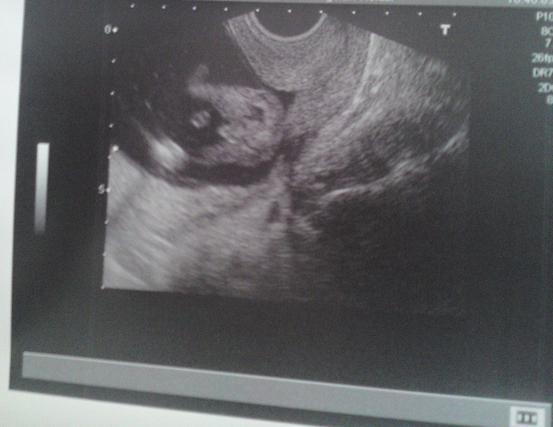

und hier noch das "Beweisfoto"

Baby geht es super, ist zeitgerecht entwickelt. SSL ist jetzt bei 9,5 cm. und es war richtig aktiv, hat kaum ne Sekunde still gehalten. schließlich hat sie zwischen den Beinchen geschaut und siehe da, es war tatsächlich ein Zipfelchen zu sehen! wir bekommen also einen Jungen!!! war im ersten Moment überrascht, weil ich mich so auf ein Mädchen versteift hatte, aber wahrscheinlich auch nur deshalb weil ich mir im Grunde ein Mädchen gewünscht habe. in letzter Zeit hatte ich und auch mein Mann aber geträumt dass es ein Junge wird.

das US-Bild ist wirklich sehr eindeutig...